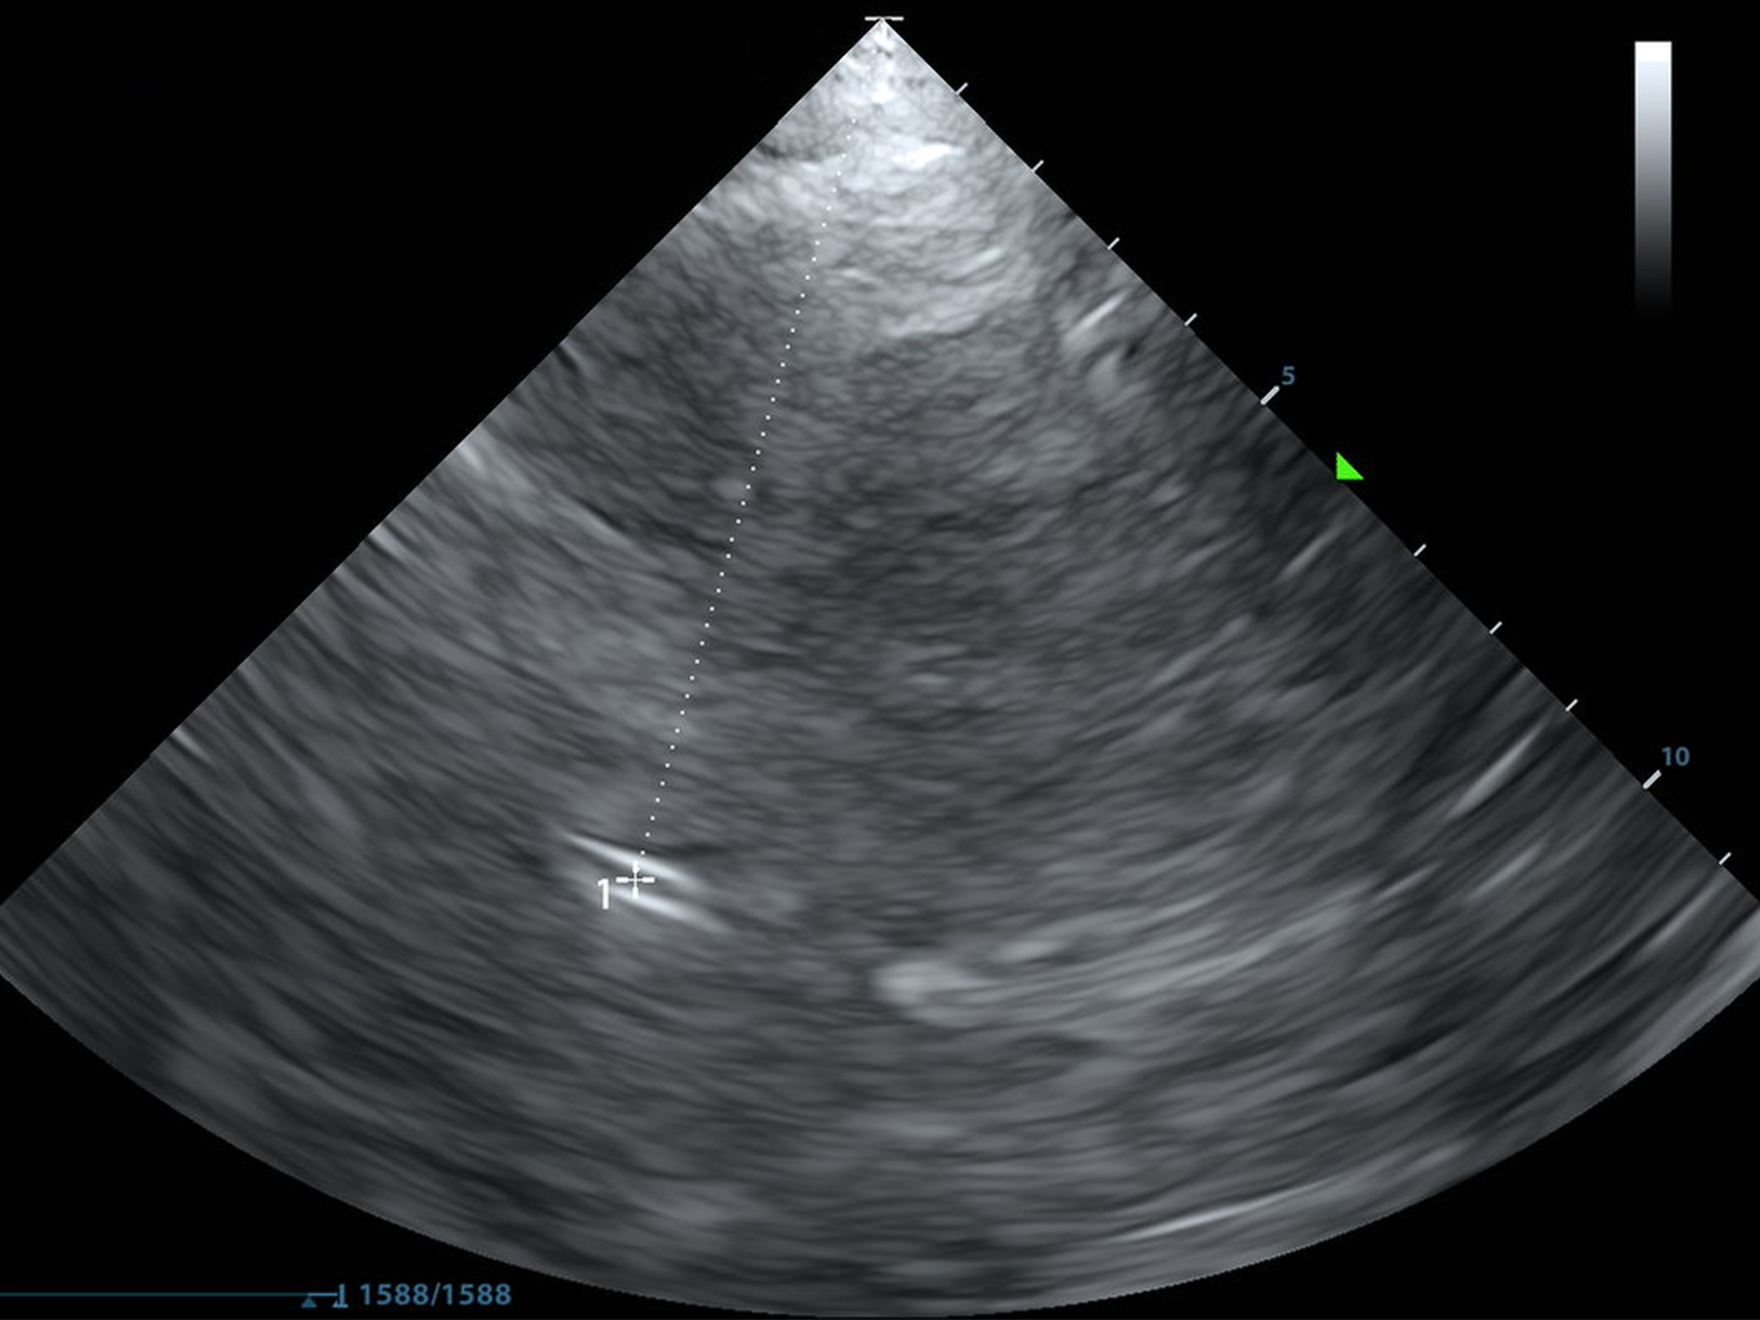

Below, you'll find a normal MCA PI. It's also majestic, virile, ruggedly-handsome, and mine.

As always, I found the MCA with color doppler and put the pulse wave doppler gate on the proximal MCA.

I selected "AutoTrace" and dragged the line from the beginning of the systolic upstroke until end diastole and the machine calculated the rest.

You can also trace the waveform with a cursor, or some machines trace it and provide the calculations without you even asking!